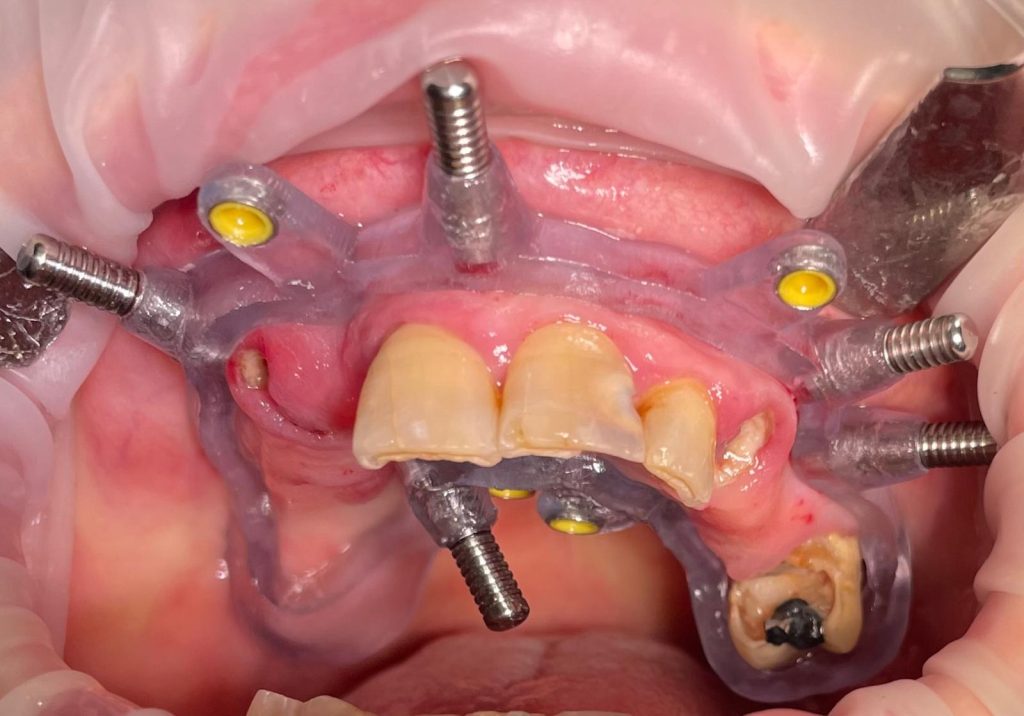

Questa settimana vi presento un caso di riabilitazione immediata dell’arcata superiore eseguita in chirurgia computer guidata con l’utilizzo di dime scomponibili.

L’intervento ha previsto l’estrazione degli elementi dentari, l’inserimento di 5 impianti nell’arcata superiore, il montaggio delle torrette provvisorie e la ribasatura del provvisorio nel cavo orale.